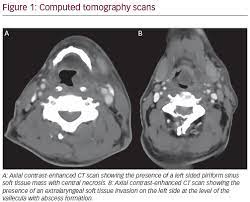

Throat Cancer Screening Raleigh Capitol Ear Nose Throat Page from www.raleighcapitolent.com What throat cancer look like. Throat cancer refers to a group of cancers that give you a tumor anywhere from your tonsils to your voice box. The symptoms of head and neck cancers can mimic those for other conditions so it is important to see your physician for a proper diagnosis. However, it is quite difficult to identify throat cancer from an early stage of the disease. For tumours of the oropharynx and hypopharynx, the patient will undergo surgical intervention if the tumour is small. Thus, throat cancer refers to those cancerous tumours which grow within the throat of an individual. Early signs of throat cancer that mimic the flu include: Throat cancer is a type of head and neck cancer that involves the pharynx and the larynx.